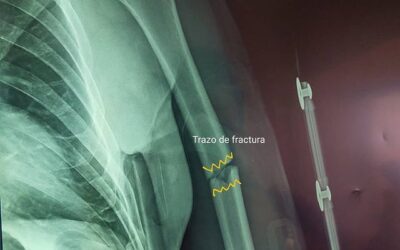

Paciente de 66 años con fractura diafisiaria de húmero izquierdo

En ésta ocasión nos tocó atender a un paciente masculino de 66 años el cual había sido diagnosticado hace 4 semanas con fractura diafisiaria de húmero izquierdo. En aquel entonces no recibió el...

Caciente posoperada de RAFI con clavo centromedular de húmero

El día de hoy acudió nuestra paciente posoperada de RAFI con clavo centromedular de húmero. Hoy acude SIN DOLOR, con una EXCELENTE movilidad del hombro, y con excelente formación de callo óseo....